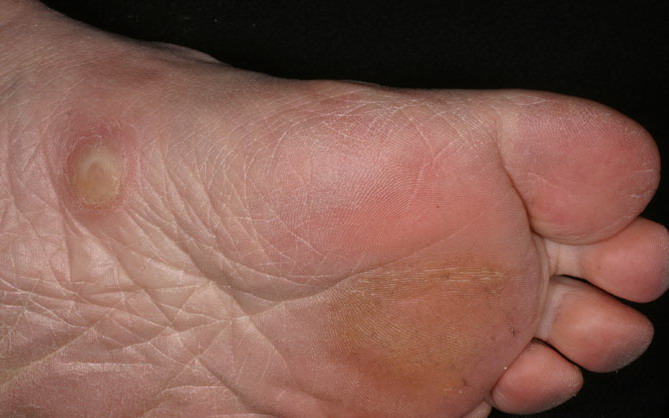

Typically, the clinical appearance of dermatofibroma is a solitary, 0.5- to 1-cm nodule. A sizable minority of patients may have several lesions, but rarely are more than 15 lesions present. The overlying skin can range from flesh to gray, yellow, orange, pink, red, purple, blue, brown, or black, or a combination of hues (see the image below). On palpation, the hard nodule may feel like a frozen pea or a small pebble fixed to the skin surface and is freely movable over the subcutis. Tenderness may be elicited with manipulation of the lesion.

The extremities are the most common sites of involvement, particularly the lower legs. Although any cutaneous site can be seen, palm and sole involvement is rare. Giant (>5 cm in diameter), atrophic, atypical polypoid, and dermatofibroma with satellitosis variants have been reported.